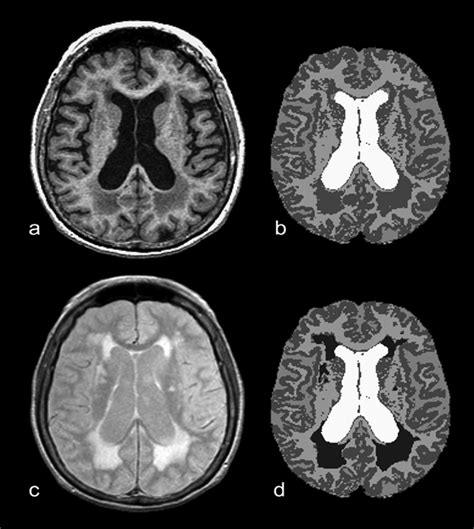

To understand this condition, we must first look at the anatomy of the brain. The brain is composed of gray matter, which contains neuronal cell bodies, and white matter, which acts as the wiring system connecting different parts of the brain. White matter consists of axons covered in a fatty substance called myelin, which helps electrical impulses travel quickly between brain regions.

Periventricular White Matter Disease occurs when the integrity of this myelin or the underlying axons is compromised in the area surrounding the brain's ventricles—the fluid-filled cavities within the brain. This is often categorized under the broader umbrella of small vessel disease. When blood flow to these deep, sensitive areas of the brain is reduced, often due to stiffening or narrowing of the small arteries, the tissue begins to show signs of damage. Radiologists often describe these areas as "hyperintensities" or "lesions" on an MRI scan.

When you look at a medical report, you may see the severity of these white matter changes graded. A common system used by neurologists is the Fazekas scale. Understanding where your results sit on this scale can help you have a more informed discussion with your healthcare provider.